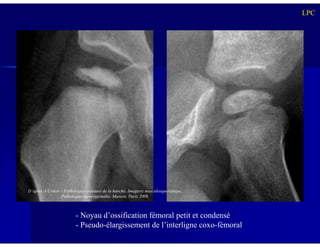

- Noyau d’ossification fémoral petit et condensé

- Pseudo-élargissement de l’interligne coxo-fémoral

D’après A Cotten – Pathologies osseuses de la hanche. Imagerie musculosquelettique.

Pathologies locorégionales. Masson, Paris 2008.